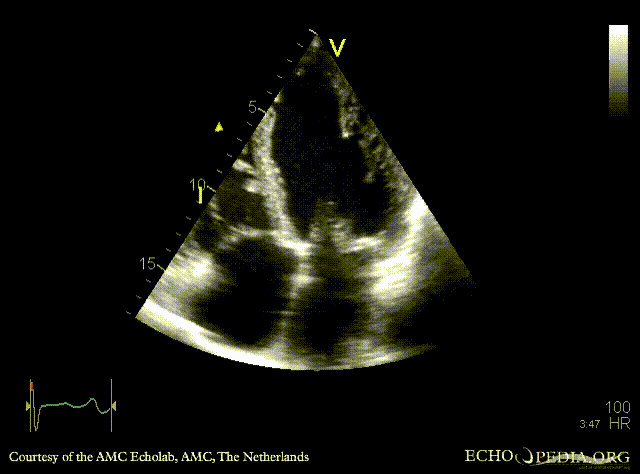

Flail of mitral valve

TEE: TEE: flail of mitral valve